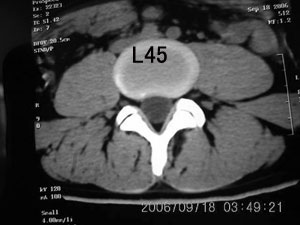

以下是引用守望可可西里在2006-9-18 21:29:00的发言:[br][br] 马尾肿瘤,密度较低,大部分似乎呈囊性变(看着很费眼),考虑室管膜瘤,建议mri。

以下是引用dyg在2006-9-18 22:27:00的发言:[br]正常脊髓.[br]分析:人的脊髓从枕大孔开始至腰1.2椎体为止,有2个生理膨大,分为颈膨大和腰膨大;该病人脊髓须然从腰段开始直至马尾似乎膨大,胆是与上段脊髓密度没有多大变化,所以我认为是正常膨大之延续;当然最好做ct增强或mri检查,排除肿瘤.

以下是引用飞虎在2006-9-18 20:18:00的发言:[br]部分椎管内密度不均且无ct值 故mri检查